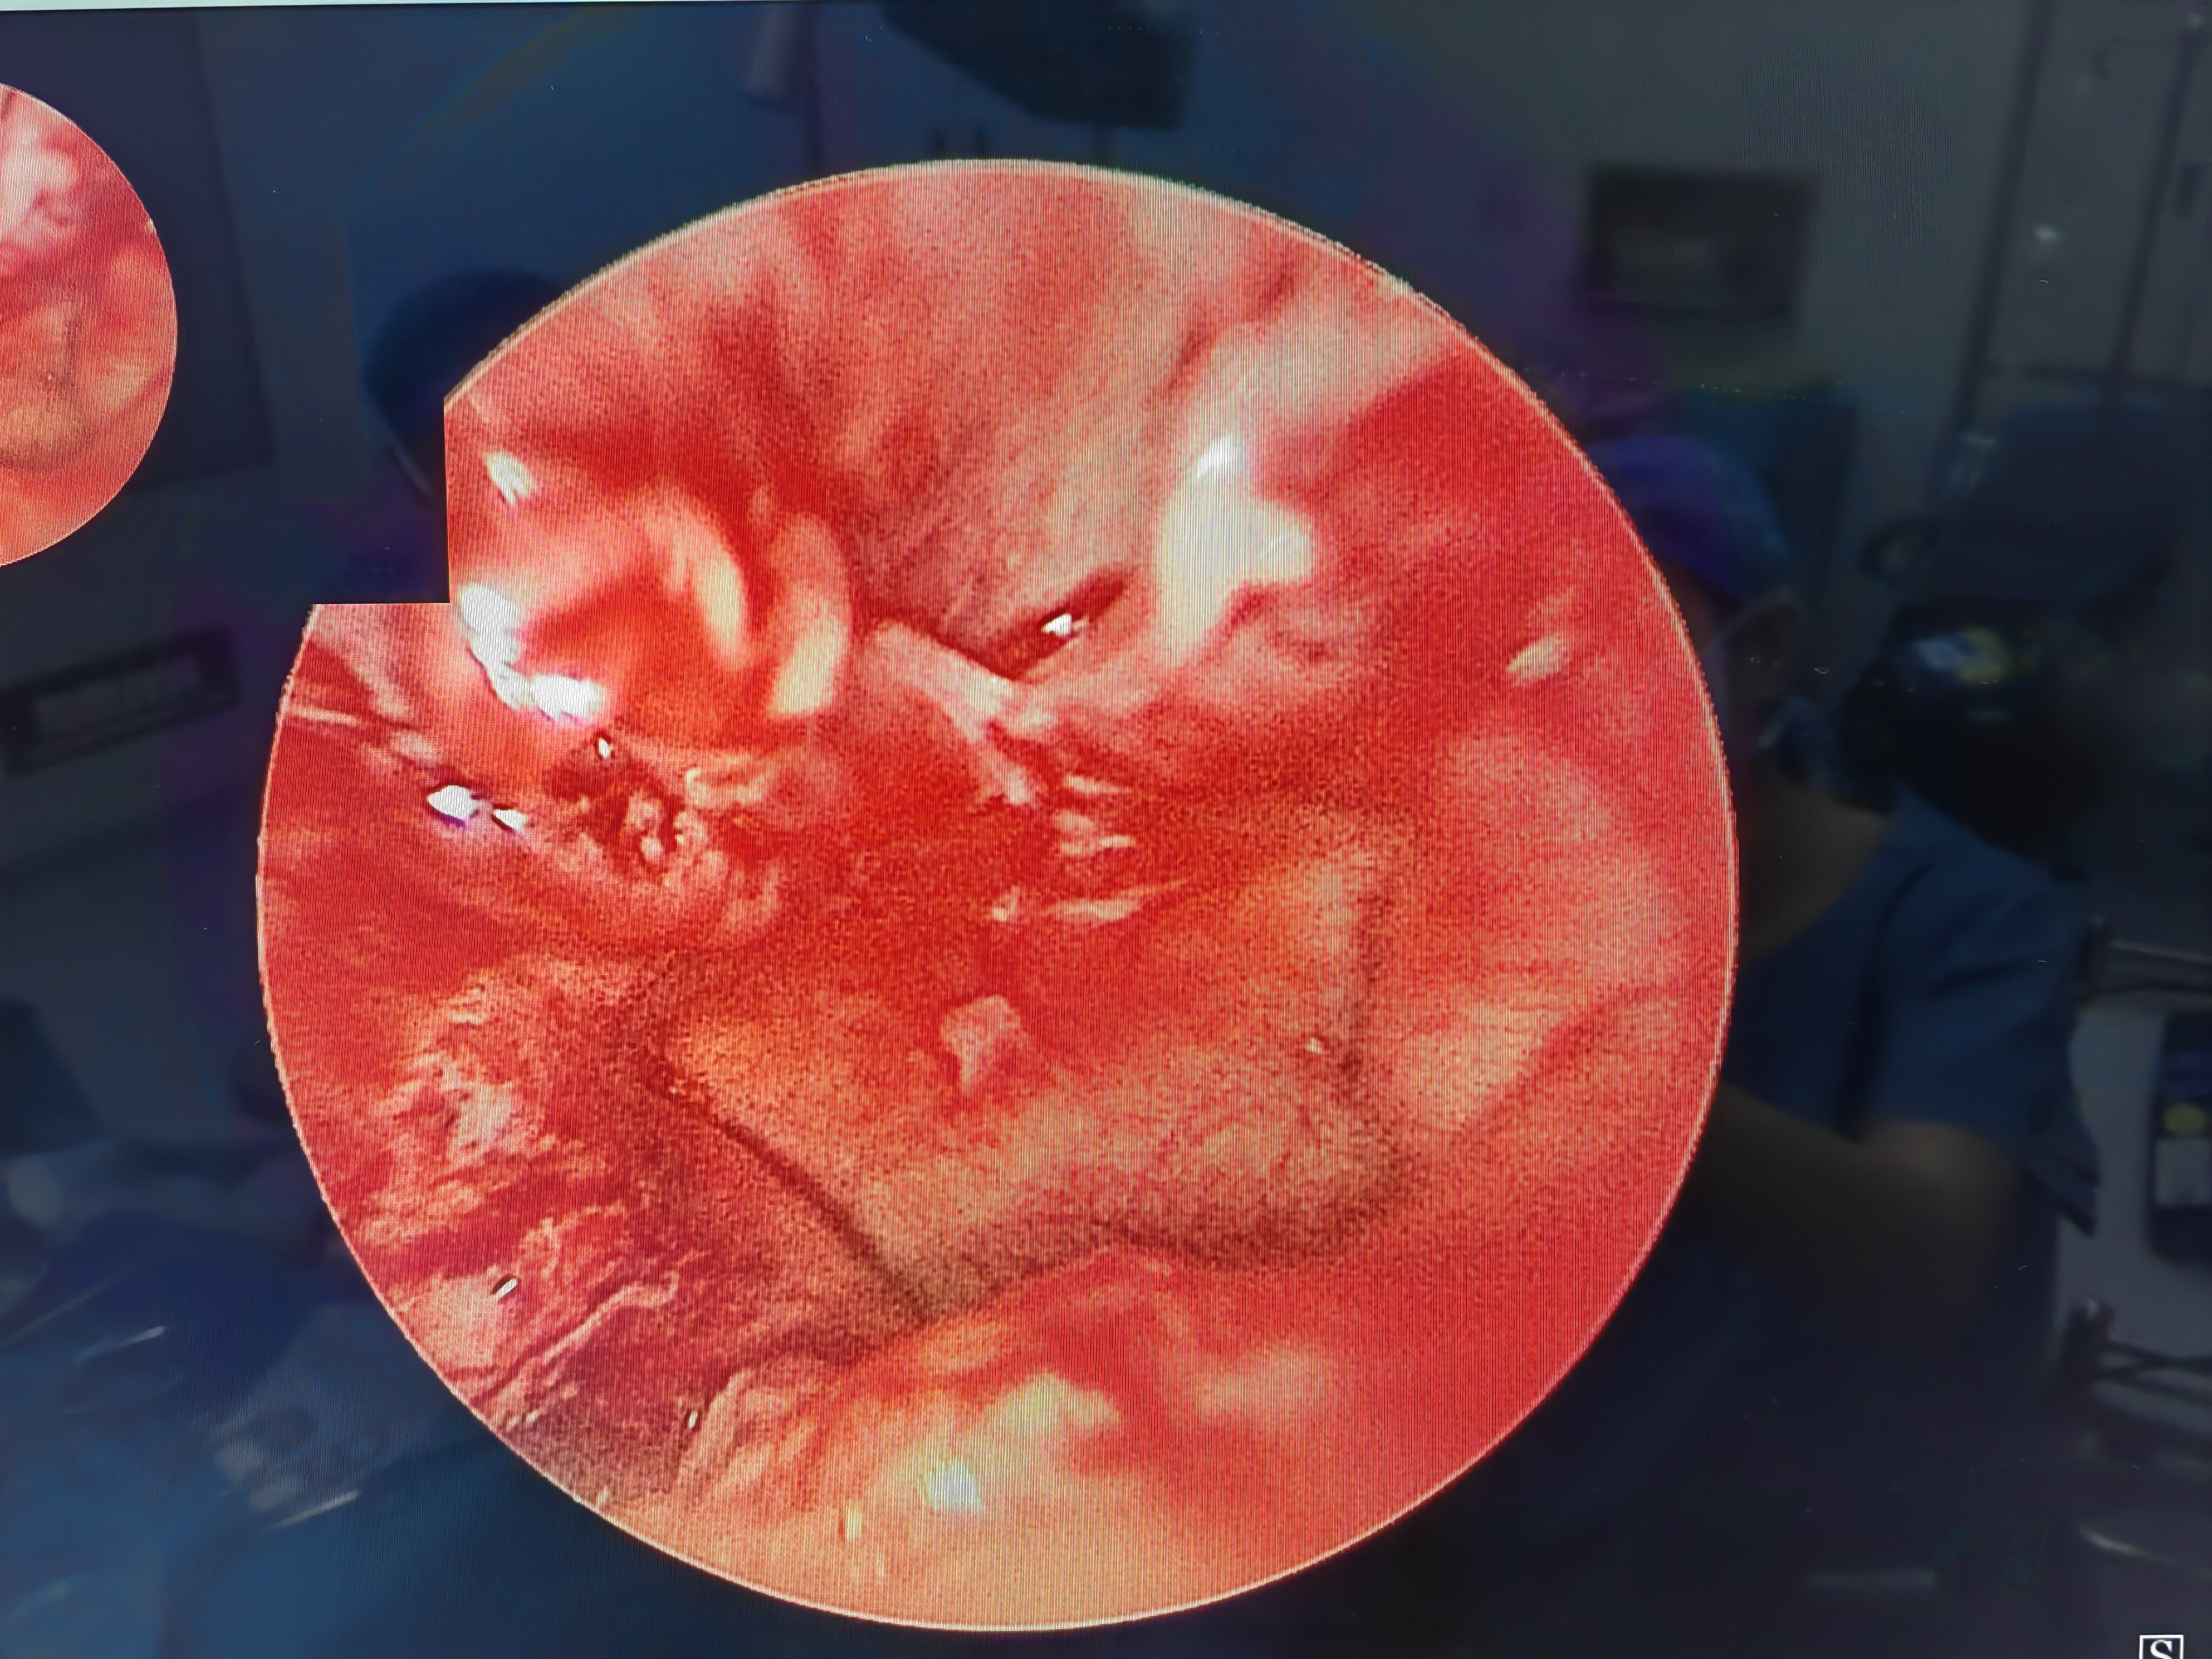

先天性后鼻孔闭锁 新生儿双侧先天性后鼻孔闭锁,表现为呼吸困难,吃奶时明显,哭闹后可暂时缓解

先天性后鼻孔闭锁是一先天性发育畸形,分单侧闭锁和双侧闭锁,双侧后鼻孔闭锁会出现周期性呼吸暂停和窒息,危及患儿的生命安全和影响鼻腔颌面部的发育,需要及时手术治疗。术后造孔容易出现再次闭锁和狭窄,常需多次手术干预,是医生和患儿家庭面临的难题。